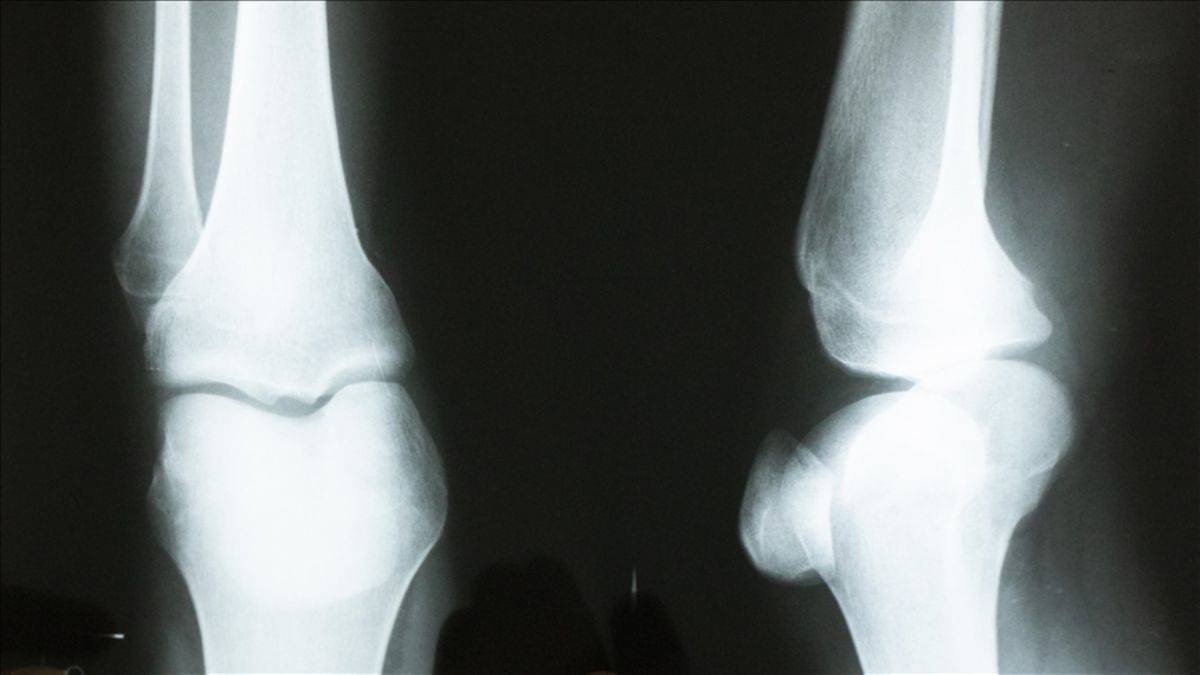

Türkiye'de ilk! Kemik yaşı yapay zeka ile tespit edilecek

Siirt Üniversitesi Öğretim Üyesi Doç. Dr. Yılmaz Kaya'nın, iki akademisyenin desteğiyle geliştirdiği, sol el bilek grafisinden kemik yaşı tespitine ilişkin sistemle ilgili makalesi uluslararası dergide yayınlandı.

Akademisyenler, kemik yaşını yapay zeka ile bir dakikanın altında sürede tespit edecek sistem geliştirdi.

Herhangi bir gerekçe ile kişinin kemik yaşı tespiti gerektiğinde el bilek görüntüsü sisteme yüklenerek, bir dakikanın altında sürede tespit yapılabilecek.

Bu kapsamda akademisyenler Özdemir ve Gedik ile yaptıkları çalışmada kemik yaşı tahmini için radyologların iş akışını hızlandıracak bir çalışma yürüttüklerini ifade eden Kaya, sol el bilek grafisinden derin öğrenme teknolojisi kullanılarak bilgisayar temelli bir karar destek sistemi geliştirdiklerini belirtti.

Verileri Kütahya'daki 4 hastaneden elde ettiklerini dile getiren Kaya, "Yapay zeka tekniklerini kullanarak el grafilerinden kişinin yaşını tespit etmeye çalıştık. Yaş tespiti çok zahmetli bir şekilde radyologlar tarafından belirleniyor ama bilgisayar sistemiyle çok daha kolay ve hızlı şekilde gerçekleştirebilirsiniz." dedi.

Kaya, el grafisinden kemik yaşı tespitinin daha önce yaklaşık 2 saat sürdüğüne işaret ederek, geliştirdikleri sistemle yaş tespit süresinin saniyelere düştüğünü kaydetti.

Öğretim görevlisi Cüneyt Özdemir de derin öğrenme yöntemiyle sol el bilek grafisinden kemik yaşı tespitine yönelik çalışmaların 18 yaş altı ve 18 yaş üstü bireylere yönelik iki aşamadan oluştuğunu belirtti.

18 yaş üstü bireylerin kemik yaşının tespitine yönelik de çalışma yaptıklarını aktaran Özdemir, "18 yaş üstü ile ilgili çalışmalar maalesef ülkemizde ve dünyada az. 18 yaş üstü kemik yaşı tespiti için yüz ve dişlerle ilgili yapılan çalışmalar var. Biz ilk defa el bilek grafisinden 18 yaş üstü kemik yaşının tespitine dönük de bir çalışma yaptık. Bu yöntemle başarılı bir sonuç elde ettik. Bu, literatürde derin öğrenme yöntemiyle 18 yaş üstü kişilerin kemik yaşı tespitine dönük yapılan ilk çalışmalardan biri olma özelliğini taşıyor." ifadelerini kullandı.